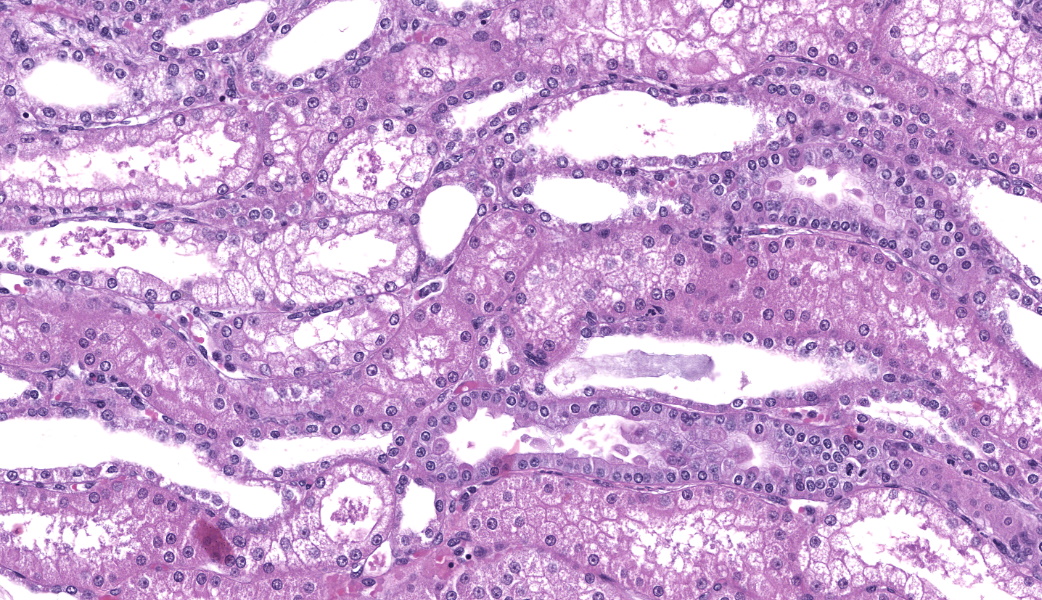

Renal lesions involve primarily the tubular component and are characterized by a variety of morphological features. Swelling and vacuolar change are prominent within proximal renal tubular epithelium, especially in the straight portion of that segment. Many tubules contain prominent cast-structures, typically consisting of granular to globular eosinophilic material, frequently admixed with blueish-gray proteinaceous sheets. Exfoliated epithelial cells are occasionally incorporated into the cast structures with numerous tubules also containing aggregates of mixed, primarily granulocytic inflammatory cells. Individually necrotic renal tubular epithelium is occasional evident. Associated with obstruction created by these casts, there is extensive, widespread tubular dilatation. Although extremely infrequent, fibrin thrombi were noted within occasional glomerular capillary loops. However, other significant glomerular changes were uncommon at the light microscopic level.

1. Renal tubular vacuolization, patchy to focally extensive, primarily proximal tubules, moderate-marked.

2. Coarsely granular eosinophilic tubular casts with occasional proteinaceous sheets consistent with myoglobin and associated myoglobinuric nephrosis, patchy, moderate, with associated marked tubular dilatation and epithelial cell thinning.

3. Acute tubular injury (ATI), patchy, mild, characterized by renal tubular epithelial cell exfoliation, individual cellular degeneration and patchy, primarily granulocytic inflammatory cell aggregates.

4. Focal glomerular capillary loop fibrin thrombi, minimal.

Kidney: Tubular vacuolization, necrosis, and regeneration, acute, multifocal, marked, with granular casts and glomerular fibrin thrombi.